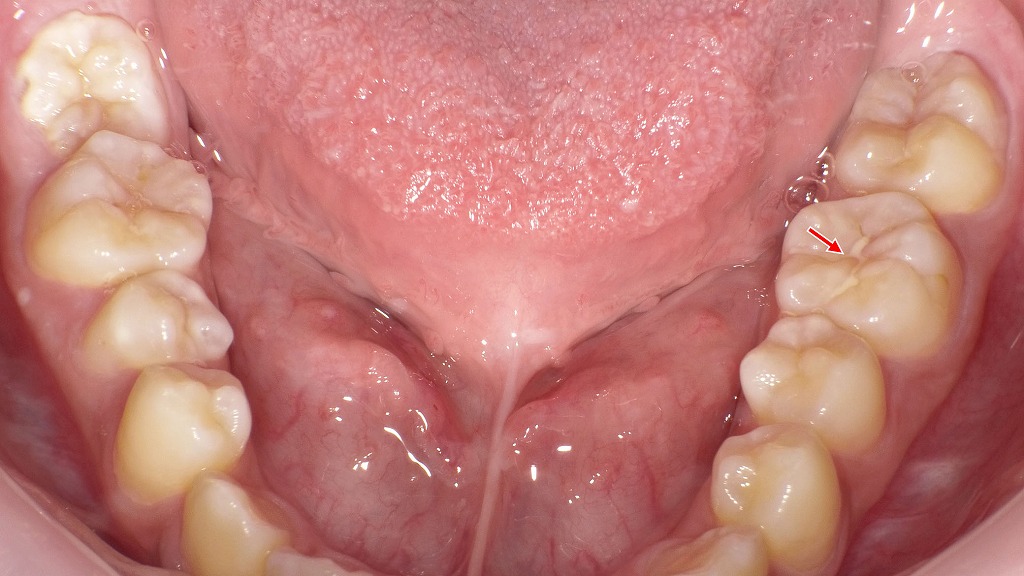

CO・C1・C2が同時に見られるむし歯進行度の実例

この口腔内写真では、緑=CO、青=C1、赤=C2 のむし歯が同時に確認できます。それぞれ進行度が異なり、同じ口の中でも段階の違うむし歯が混在しています。

🔵 C1(シーワン:エナメル質むし歯)

- エナメル質内に限局した浅いむし歯

- 白・黄・茶色の変色として見えることがある

- 穴がごく浅く、触診やレントゲンで判別

- 画像の青矢印が示す部分は表面や溝に着色・変化がある部位

🔴 C2(シーツー:象牙質むし歯)

- エナメル質を越えて象牙質まで進行したむし歯

- 茶色〜黒色に変色し、はっきりとした欠損(穴)が見える

- 冷たい物がしみる、痛みが出やすい

- 赤矢印で示されている部分は象牙質が露出し、欠損が明確な部位

COとC1の判定が難しい理由

- COもC1も「白濁」「色の変化」だけでは見た目が似ている

- 肉眼では 表層の脱灰なのか、内部が進行しているのか を判別できない

そのため、白い変化=COとは限らず、白濁していてもC1の場合があるという点が重要です。